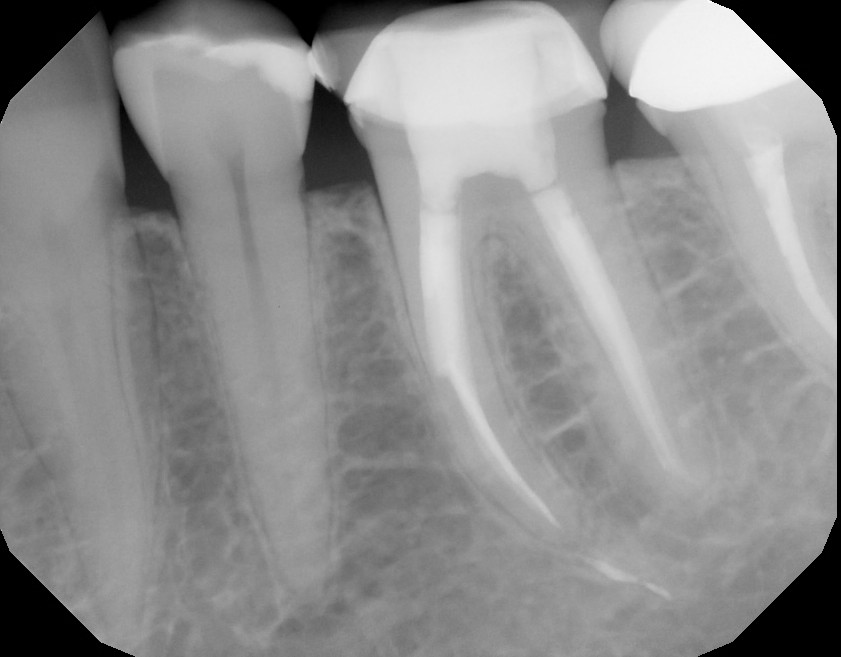

A long separated file removal by Dr. Farzad Danesh Pure Practical Endo File Separation instrument separation during endodontic therapy is a frequent accident with rotary instruments being more likely to separate than. instrument separation is one of the most routinely encountered mishaps occurring in the arena of endodontics. separation of endodontic files is not a common incident in clinical practice. clinicians may have fractured a file and then successfully retrieved. Endo File Separation.

The Endo Blog CBCT as Aid In Removal of Separated File Endo File Separation instrument separation during endodontic therapy is a frequent accident with rotary instruments being more likely to separate than. separation of endodontic files during root canal treatment is a common multifactorial problem facing most of. separation of endodontic files is not a common incident in clinical practice. instrument separation is one of the most routinely encountered mishaps. Endo File Separation.

Separated Endodontic Instruments Pocket Dentistry Endo File Separation instrument separation during endodontic therapy is a frequent accident with rotary instruments being more likely to separate than. separation of endodontic files during root canal treatment is a common multifactorial problem facing most of. separation of endodontic files is not a common incident in clinical practice. separation of endodontic instruments within the root canal is an. Endo File Separation.